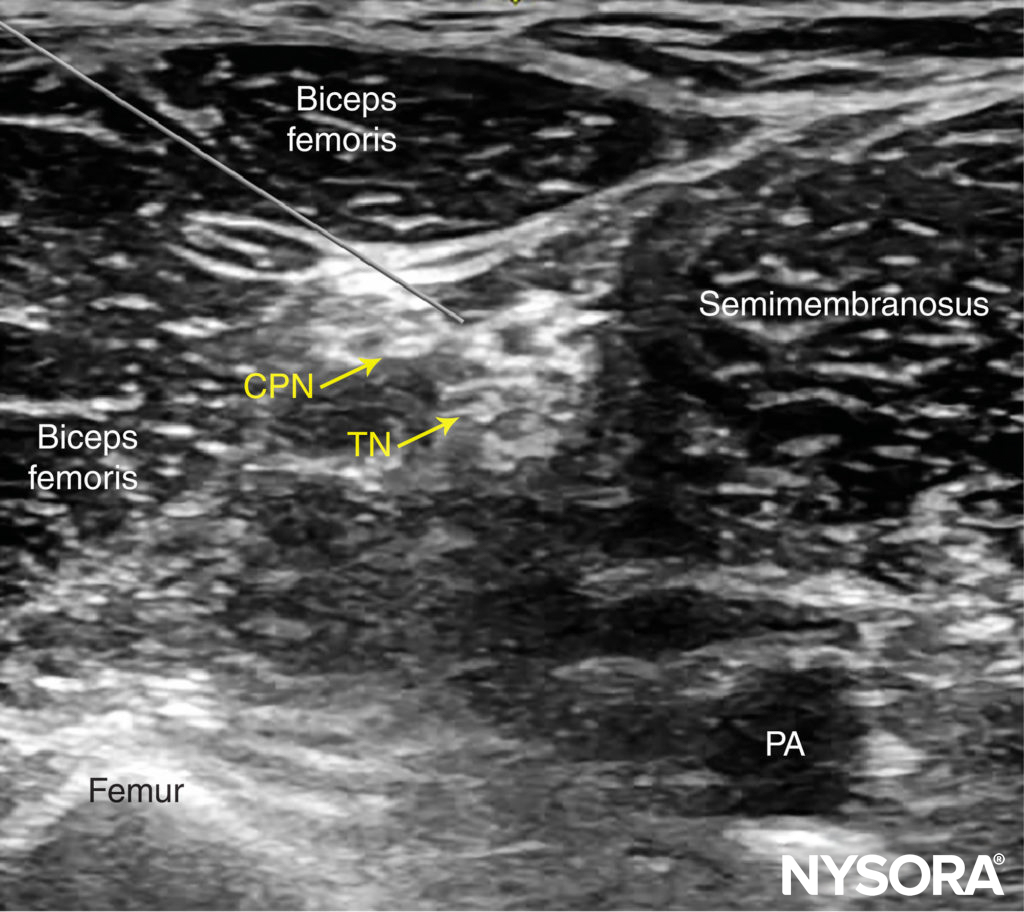

For the posterior approach, the needle is inserted in plane from lateral to medial (Figure 9) or out of plane (Figure 10). If nerve stimulation is used (0.5 mA, 0.1 msec), the contact of the needle tip with either branch of the nerve usually is associated with a motor response of the calf or foot. Once the needle tip is placed within the common sciatic nerve sheath, 1–2 mL of local anesthetic is injected to confirm the proper injection site. Such injection should result in a distribution of local anesthetic within the sheath, and separation of the TN and CPN within Vloka’s sheath (Figure 11).

FIGURE 9. Simulated needle path and needle tip placement to nerve block the sciatic nerve (TN and CPN) through the posterior approach, in plane from lateral to medial. PA, popliteal artery.

FIGURE 10. Simulated needle path and proper needle tip placement to nerve block the sciatic nerve (TN and CPN) through the posterior approach out of plane. PA, popliteal artery.

- In the posterior approach to the popliteal nerve block, either an in-plane (lateral or medial) or out-of-plane technique can be used (Figures 9 through 12). While the in-plane lateral approach is commonly used, the advantage of the out-of-plane approach is that the needle path is through the skin and adipose tissue rather than the muscles and thus, less painful.